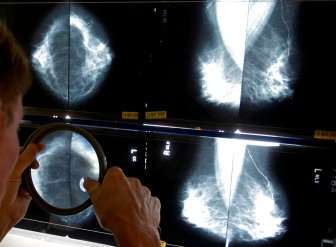

Mammograms

Alberta lowers age for women to be screened for breast cancerAlberta Health Services has lowered the recommended age for biennial breast cancer screening for average-risk women from 50 to 45.HealthOct 18, 2022

Cancer foundations in Saskatchewan launch fundraiser to save the ‘Breast Screening Bus’Since 2002, the Breast Screening Bus provided mammograms for residents in rural and remote communities of Saskatchewan, but funding is now needed for a new bus.HealthOct 3, 2022

15 patients in N.L. require followup as review of thousands of mammograms continuesThe province's health authorities have identified 15 patients this week requiring further followup as a review continues of thousands of mammograms.HealthSep 15, 2022

‘How the hell did this happen?’ More than 16,500 mammograms under review across N.L.Officials from three of the province's four health authorities told reporters the approximately 13,884 mammograms under scrutiny represent about 11,751 patients.HealthAug 31, 2022

Newfoundland health authority reviewing about 3,000 mammograms for possible issuesThe health authority will review its mammogram viewing procedures and look at whether this error occurred because staff had been working from home during the COVID-19 pandemic.HealthAug 24, 2022

Disabled women in Quebec still struggling with mammogram access: advocatesA community group advocating for people with disabilities claims some women are having trouble getting access to mammograms.CanadaMay 4, 2022

AI can spot breast cancer better than humans, study findsArtificial intelligence programs are better at spotting cancer than humans, a new study suggests. What does that mean for cancer detection?HealthJan 1, 2020

Many women aren’t told they have dense breasts. Here’s why it matters43 per cent of women ages 40 to 74 have dense breasts, and they can have serious implications.LifestyleOct 3, 2019

New breast cancer screening guidelines are outdated and dangerous, experts sayMore than 130 breast-cancer doctors and researchers disagree with new screening recommendations, saying the task force is basing their recommendations on outdated data.HealthJan 28, 2019

Patients should decide when to get mammograms: Canadian health expertsNew guidelines from the Canadian task force on preventive health are empowering women to take charge of their health when it comes to breast cancer screening.HealthDec 10, 2018